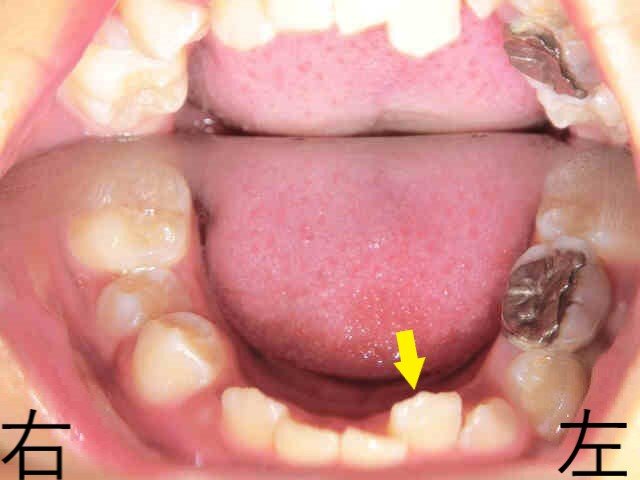

掲載の写真は、前歯の噛み合わせを下から見上げた状態を撮影したものです。

前歯の噛み合わせが深く(ディープバイト)、下からのぞいても下顎前歯の全体を確認できない状態でした。

上の前歯が目立つため「出っ歯」と表現されることが多いようですが、実際には下顎が後方に位置しているため、相対的に上顎が前に出ているように見えるケースもあります(下顎の劣成長)。